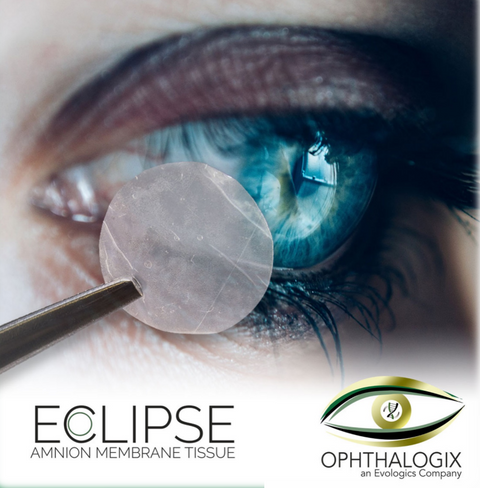

Eclipse Dehydrated Dual Layer Amniotic Membrane by Ophthalogix

Eclipse is a dehydrated amniotic membrane allograft disc used to improve surgical outcomes including procedures in Ophthalmology and Optometry.

Eclipse is a precision crafted single layer membrane for use in mild to severe conditions. A thicker single layer provides the same growth factors as dual layers while retaining the patient comfort of single layer membranes.

Eclipse has the following advantages:

• Eclipse is air-dried not freeze-dried

• Eclipse can be kept at room temperatures, eliminating the need for freezer

• Suitable for immediate use off the shelf

• Hydrates rapidly

• Adheres to the ocular surface

• Sterilized with gamma radiation to SAL 10-6 in accordance with ISO 11137

• Textured surface facilitates ease of handling and placement

• Symmetric graft allows either side to be placed in contact with ocular surface

• Can be placed in either direction (multi-directional graft)

• Has a micron thickness of 30-35 Microns

• Tackier stromal surface for better adherence

• Only 9 units of KiloGray used to sterilize the grafts

• Low doses of radiation retainin more growth factors

• New foil packaging offers a 5-year shelf life

• More growth factors and cytokines to survive the sterilization process